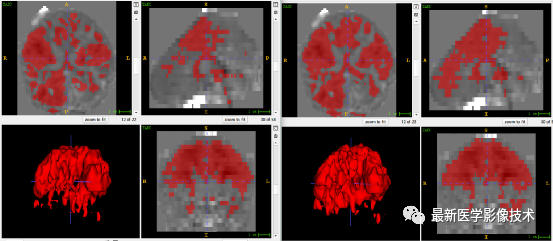

5、验证集分割结果

左图是金标准结果,右图是预测结果。